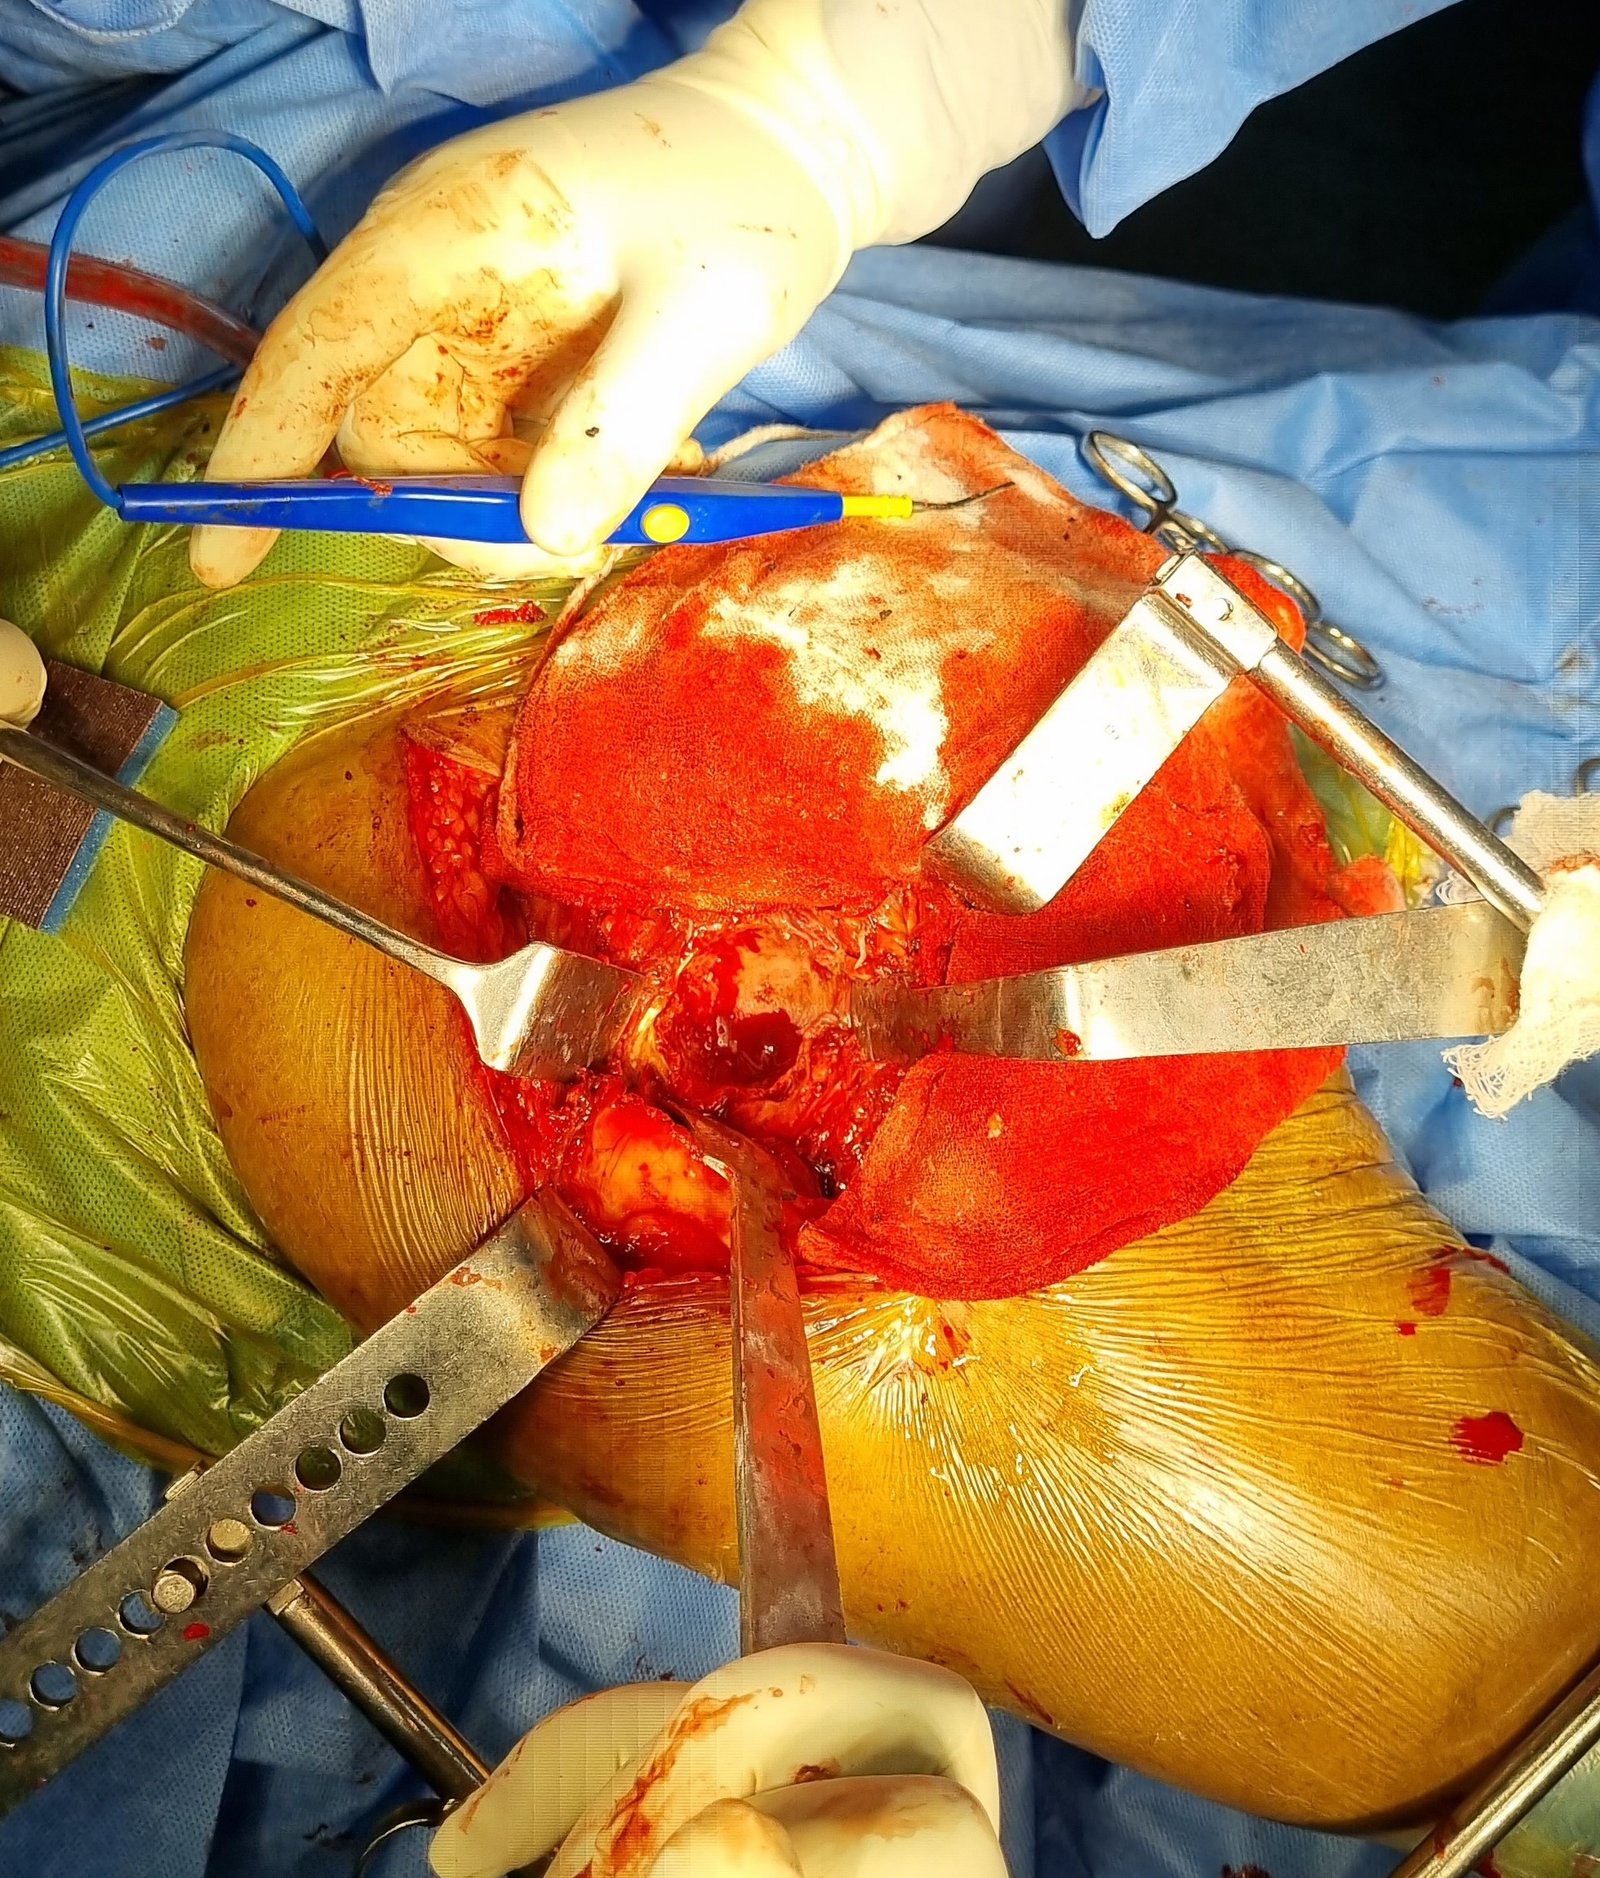

Intra-Op (Photos)

Non Union & Fixation Failure Post CHS